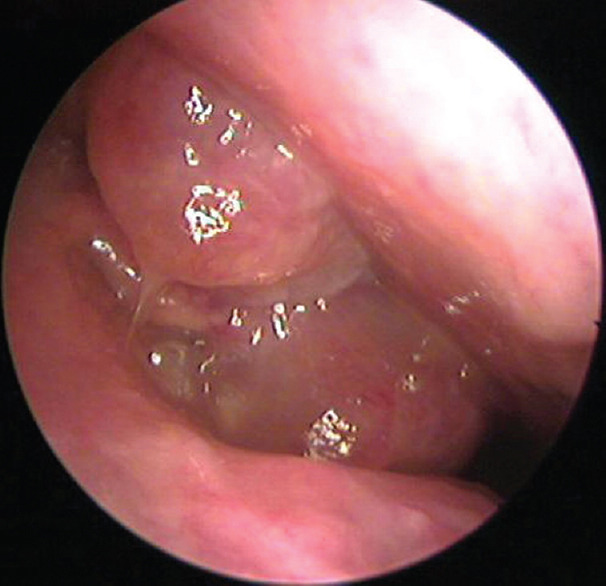

Background: Patients having nasal polyposis who do not respond to medical management are subjected for functional endoscopic sinus surgery (FESS). One of the most common complications of surgery is bleeding. One of the strategies to reduce bleeding and securing a dry operating field during surgery is the use of preoperative corticosteroids which shrink the polyps and decrease mucosal inflammation.